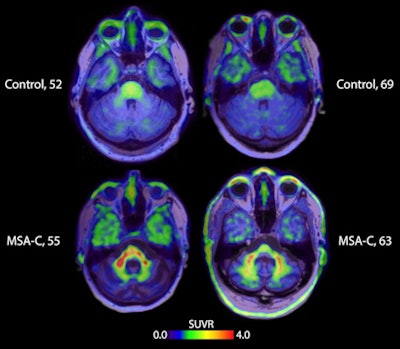

Brain scans taken with the tracer strongly indicate the signal specificity for alpha-synuclein in MSA patients, compared with healthy volunteers and patients with other alpha-synucleinopathies, like Parkinson's disease and Lew Body Dementia. The results represent the potential for earlier and more reliable differentiation for MSA, lead researcher, Dr. Oskar Hansson, PhD, of Lund University, said in a press release.

Furthermore, the tracer showed target engagement in vivo in alpha-synucleinopathies with a pharmacokinetic and safety profile suitable to be developed as a human brain PET imaging agent. Specifically, the ACI-12589 data showed enhanced contrast and alpha-synuclein target specificity in those with MSA. Tracer retention was highest in areas affected by MSA disease processes, particularly cerebellar white matter, according to the trial results.